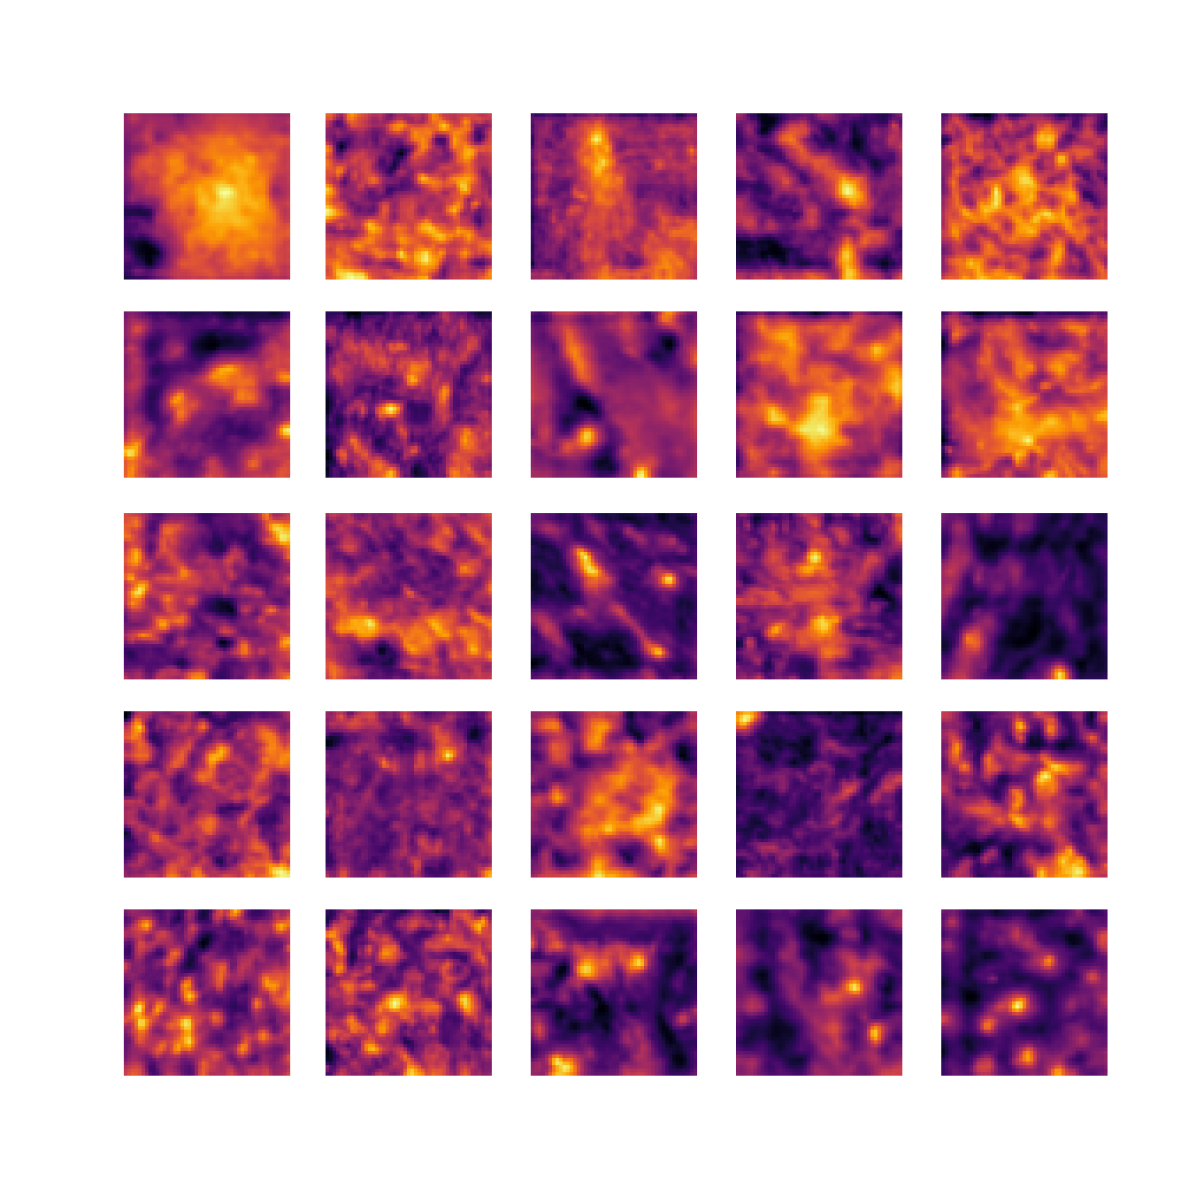

We also analyse the activation maps for each model using GradCAM as described in section S3. This offers more insight into the areas of the image which are contributing most heavily to the models’ representations. In Figure 4(b) we present some representative examples, however, a larger selection which was chosen at random is presented in Figures S10 to S25. The larger selection makes it easier to see the emergent patterns, including that privileged Siamese models tend to mainly identify features which are strongly present in both inputs, while unprivileged Siamese models tend to learn more diffuse features that are not specific to one cell phenotype or image region. TriDeNT ♆ incorporates both sets of features, learning both features specific to the privileged data and more the general features associated with unprivileged Siamese networks.

We can see in Figure 4(b) panel A that for ERG, the privileged Siamese model focuses almost exclusively on any nuclei which could be endothelial cells. As there are very few endothelial cells in the dataset, it could be an effective strategy to identify anything that could potentially be an endothelial cell to minimise the difference between the representations of the H&E model and the IF mask model. In the corresponding unprivileged Siamese image, we see that the model identifies some of these nuclei, albeit less strongly, but also focuses heavily on the other tissue and even the background, while strongly fixating on two spots of debris in the center of the image. This model has less ‘incentive’ to learn the weak features related to endothelial cells as these occur rarely and are not easy to detect, while more generic strong features such as the presence of connective tissue and the prevalence of background are more common and predictable from augmented images. We see that TriDeNT ♆ combines these two feature sets, strongly identifying nuclei while also identifying the connective tissue.

In panel C we see a similar pattern, with the privileged Siamese model fixating solely on the nuclei, while the TriDeNT ♆ model takes a more balanced approach. The unprivileged Siamese model appears to focus on a single cluster of nuclei while neglecting others, and similarly identifies an area of fibroblasts with its distinctive pattern but does not others.

In contrast to panels A and C which represent models with poor privileged Siamese results, panels B and D represent models whose privileged Siamese results were comparable to both TriDeNT ♆ and even the supervised baseline. It is therefore interesting to note that there are far more similarities between the privileged Siamese and TriDeNT ♆ models in both cases. Particularly in panel B, TriDeNT ♆ and the privileged Siamese model return virtually identical heatmaps, with both strongly identifying epithelial nuclei and neglecting the same areas of connective tissue. The unprivileged model in this case appears to focus solely on the centre of the image, giving a significantly different heatmap to the other panels.

Panel D again shows the previous pattern, with the privileged Siamese model identifying the features strongly present in the privileged data – fibroblasts – while neglecting the nuclei present. TriDeNT ♆ also strongly identifies the connective tissue, but, unlike the privileged Siamese model, does not completely neglect the nuclei. The unprivileged Siamese model primarily identifies background, and does not appear to identify the nuclei in this example.